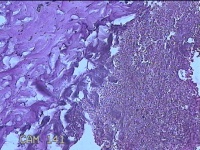

性别

女

年龄

27岁

临床诊断

乳腺脓肿

一般病史

发现右侧乳腺脓肿1个月余,伴局部疼痛不适。

标本名称

右侧乳头下方结节

大体所见

灰白暗红色结节0.8x0.5x0.3cm一个,表面糜烂。

图1

组织没固定好